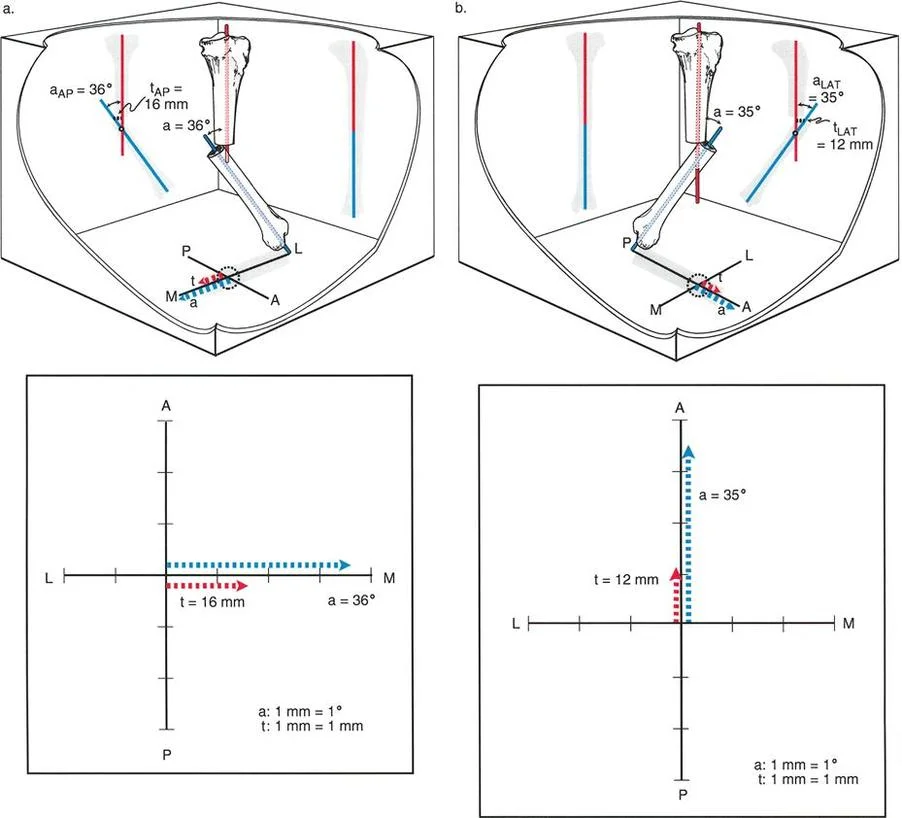

بمجرد الحصول على صور التصوير الشعاعي عالية الجودة، يقوم الأستاذ الدكتور محمد هطيف بإجراء تحليل هندسي دقيق باستخدام مبادئ الدكتور بالي:

- رسم المحاور: يتم رسم خطوط المحور الوسطي للعظم (mid-diaphyseal axis lines) للأجزاء القريبة والبعيدة من العظم المصاب على كل من الأشعة السينية الأمامية الخلفية والجانبية.

- تحديد مركز دوران الانحراف (CORA) أو نقطة الانحراف-الانزياح (a-t point): هذه هي النقطة التي تتقاطع عندها خطوط المحور، وتُعد "القمة الحقيقية" للتشوه. تحديدها بدقة أمر بالغ الأهمية لتخطيط مكان قطع العظم.

- قياس الانحراف والانزياح: تُستخدم قياسات دقيقة لتحديد حجم الزاوية (الانحراف) ومقدار التحرك الجانبي (الانزياح).

- تقييم انحراف المحور الميكانيكي (MAD): يُحسب مدى انحراف المحور الميكانيكي عن مركزه الطبيعي في الركبة.

فهم أبعاد التشوه: قياسات بالي المتقدمة

إن فهم تشوهات الانحراف والانزياح العظمي يتجاوز مجرد رؤية انحناء أو انزياح في الأشعة السينية. يتطلب الأمر تحليلًا هندسيًا دقيقًا لتحديد الأبعاد الحقيقية للتشوه. هذه القياسات هي حجر الزاوية في التخطيط الجراحي الناجح، وهي ما يميز جراحة تصحيح التشوهات المتقدمة.

قياس الانزياح بوجود انحراف

بينما يُعد قياس الانزياح الخالص أمرًا بسيطًا (المسافة العمودية بين خطين متوازيين)، يصبح الأمر أكثر تعقيدًا عند وجود انحراف زاوي، حيث لم تعد خطوط المحور متوازية بل تتقاطع.

وفقًا لمبادئ الدكتور بالي، هناك طريقتان أساسيتان لقياس حجم الانزياح في وجود تشوه زاوي، وكلاهما يتطلب رسم خطوط المحور الوسطي للعظم (mid-diaphyseal axis lines) للجزء القريب والبعيد من العظم.

طريقة المرجع القريب (The Proximal Reference Method):

- في هذا النهج، يُقاس الانزياح كمسافة عمودية من خط المحور القريب إلى خط المحور البعيد، وتُقاس تحديدًا عند مستوى الطرف القريب من الجزء البعيد (موقع الكسر أو قطع العظم).

- لماذا هي مفضلة سريريًا؟ تُفضل هذه الطريقة بشكل كبير، خاصة عند وجود قصر في الطرف. إذا تم الإشارة إلى القصر بالنسبة لخط المحور القريب، فإن مقدار الانزياح المقاس يظل ثابتًا بغض النظر عن مقدار تقصير أو إطالة الطرف. يعمل الجزء القريب كنظام إحداثيات ثابت، مما يجعل هذه الطريقة قوية رياضيًا أثناء التخطيط قبل الجراحة لإطالة العظام أو تصحيحها.

طريقة المرجع البعيد (The Distal Reference Method):

- بدلاً من ذلك، يمكن قياس الانزياح كمسافة عمودية من خط المحور البعيد إلى خط المحور القريب، وتُقاس عند مستوى الطرف البعيد من الجزء القريب من العظم.

- التحدي: على الرغم من صحتها هندسيًا، تُدخل هذه الطريقة متغيرًا مربكًا: طول الطرف. إذا كان هناك قصر محوري، واستخدمت المحور البعيد كنقطة مرجعية، فإن حجم الانزياح المقاس سيتغير اعتمادًا على درجة القصر. يحدث هذا لأن المحور البعيد منحرف بالنسبة للمحور القريب؛ فكلما حركت الجزء البعيد باتجاه القريب (تقصير)، تتغير المسافة العمودية بين المحورين في موقع الكسر.